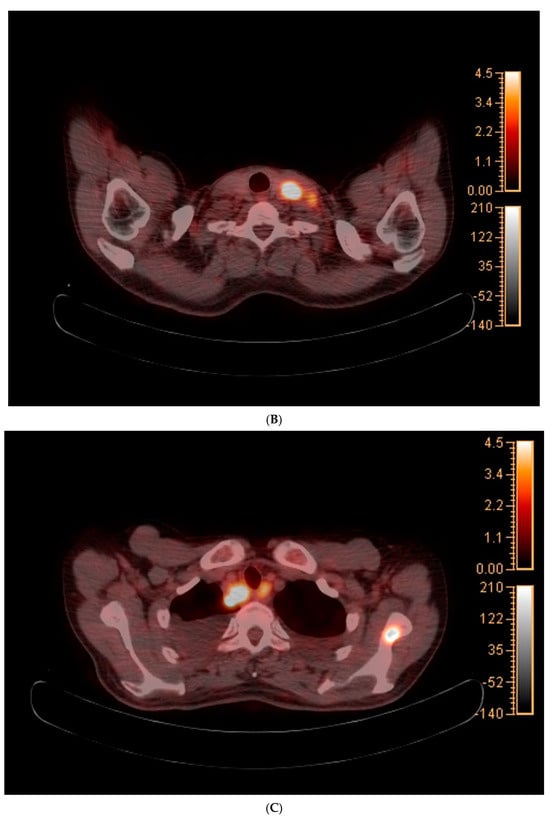

The chest radiography showed a massive right-sided pleural effusion (Figure 1A). Percutaneous catheter drainage was performed for the right-sided pleural effusion. The chest computed tomography showed a 3.3 cm × 3.0 cm mass in the right upper lobe (Figure 1B). The positron emission tomography/computed tomography revealed metastases in the left-sided supraclavicular lymph nodes, multiple bilateral mediastinal lymph nodes, and left scapula (Figure 2). The magnetic resonance imaging of the brain revealed multiple tiny cerebral and right cerebellar metastases (Figure 3). A percutaneous needle biopsy confirmed the diagnosis of lung adenocarcinoma (pT2aN3M1c, stage IVB); the analysis of the right-sided pleural effusion revealed metastatic adenocarcinoma. The genetic analysis revealed an exon 19 deletion in the EGFR gene. The laboratory tests, including the blood cell counts and chemistry, were within the normal ranges prior to treatment initiation. The patient was administered the EGFR-TKI afatinib (40 mg/day) as a first-line chemotherapy.

Figure 2.

(A–E) Positron emission tomography/computed tomography revealed metastases to multiple lymph nodes, includingleft supraclavicular lymph node, bilateral mediastinal areas, and left scapula.